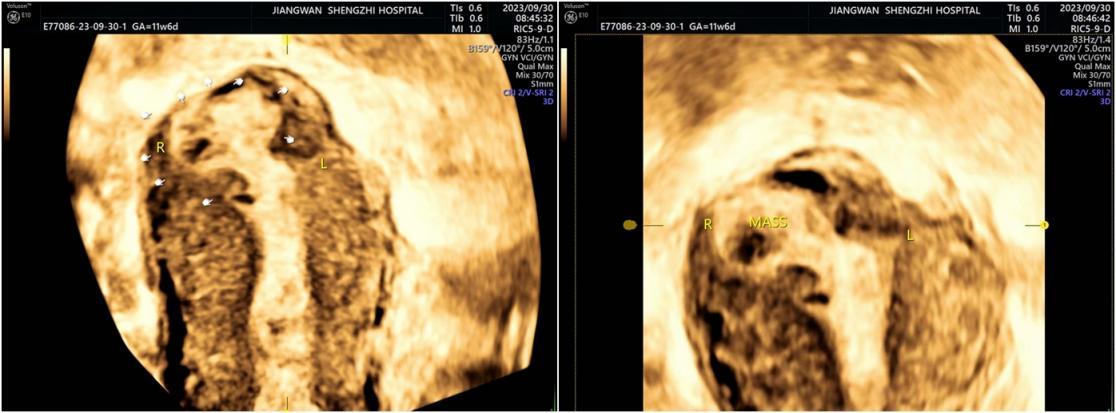

三维超声图像

3、间质部妊娠包块不与宫腔相连接,存在“间质线特征”。“间质线特征”是输卵管间质部妊娠的特异超声表现,指在宫底横切面宫角区域,自子宫体腔外侧与孕囊或妊娠包块之间的线状高回声,对于间质部妊娠诊断的特异度和敏感度很高。

与二维超声相比,三维超声能够更好显示间质部妊娠病灶的整体结构及内部细微结构,明确病灶位置及分型,更直观、立体,往往可以发现无症状的患者,诊断准确率可达93.55%【以上数据来自于《输卵管间质部妊娠诊治的中国专家共识(2022年版)》】。